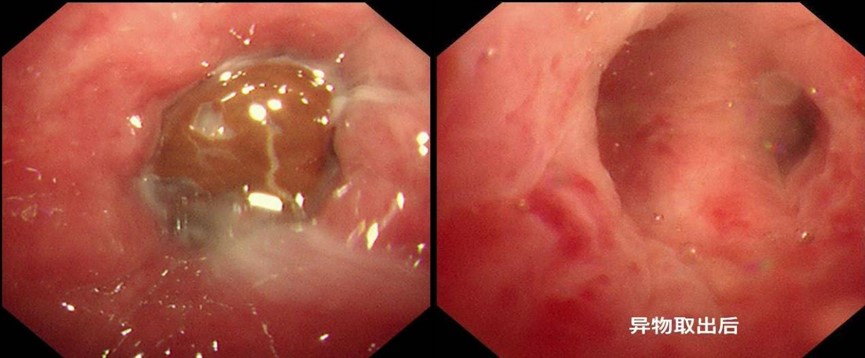

手术当日,苏大附四院多学科团队紧密配合。麻醉科精准调控麻醉深度,在保障患者安全的同时,为手术创造良好条件。蒋军红、曾大雄主任熟练操控气管镜,气管下段气切口位置呈刀鞘样改变,镜下发现堵塞右肺中叶气管的“真凶” 竟是一颗红豆,周围黏膜充血水肿严重。

凭借丰富经验,团队通过活检钳和异物网篮钳取异物后,成功将滞留月余的异物取出,并见大量脓性分泌物溢出。随着气道恢复通畅,这场与异物的“博弈”终于顺利收官。